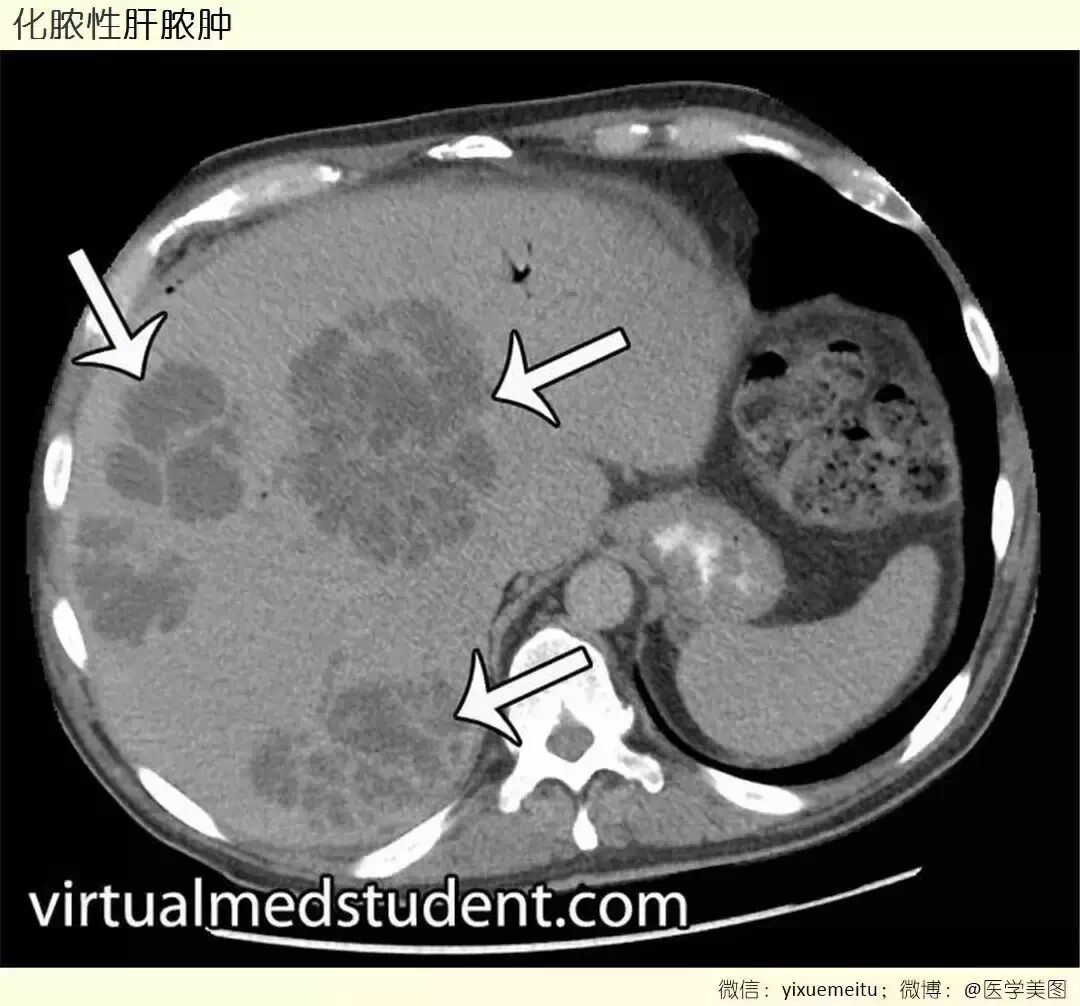

临床笔记 l 化脓性肝脓肿